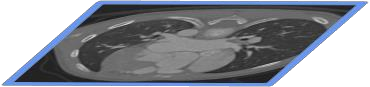

The success of deep learning heavily depends on the availability of large labeled training sets. However, it is hard to get large labeled datasets in medical image domain because of the strict privacy concern and costly labeling efforts. Contrastive learning, an unsupervised learning technique, has been proved powerful in learning image-level representations from unlabeled data. The learned encoder can then be transferred or fine-tuned to improve the performance of downstream tasks with limited labels. A critical step in contrastive learning is the generation of contrastive data pairs, which is relatively simple for natural image classification but quite challenging for medical image segmentation due to the existence of the same tissue or organ across the dataset. As a result, when applied to medical image segmentation, most state-of-the-art contrastive learning frameworks inevitably introduce a lot of false-negative pairs and result in degraded segmentation quality. To address this issue, we propose a novel positional contrastive learning (PCL) framework to generate contrastive data pairs by leveraging the position information in volumetric medical images. Experimental results on CT and MRI datasets demonstrate that the proposed PCL method can substantially improve the segmentation performance compared to existing methods in both semi-supervised setting and transfer learning setting.